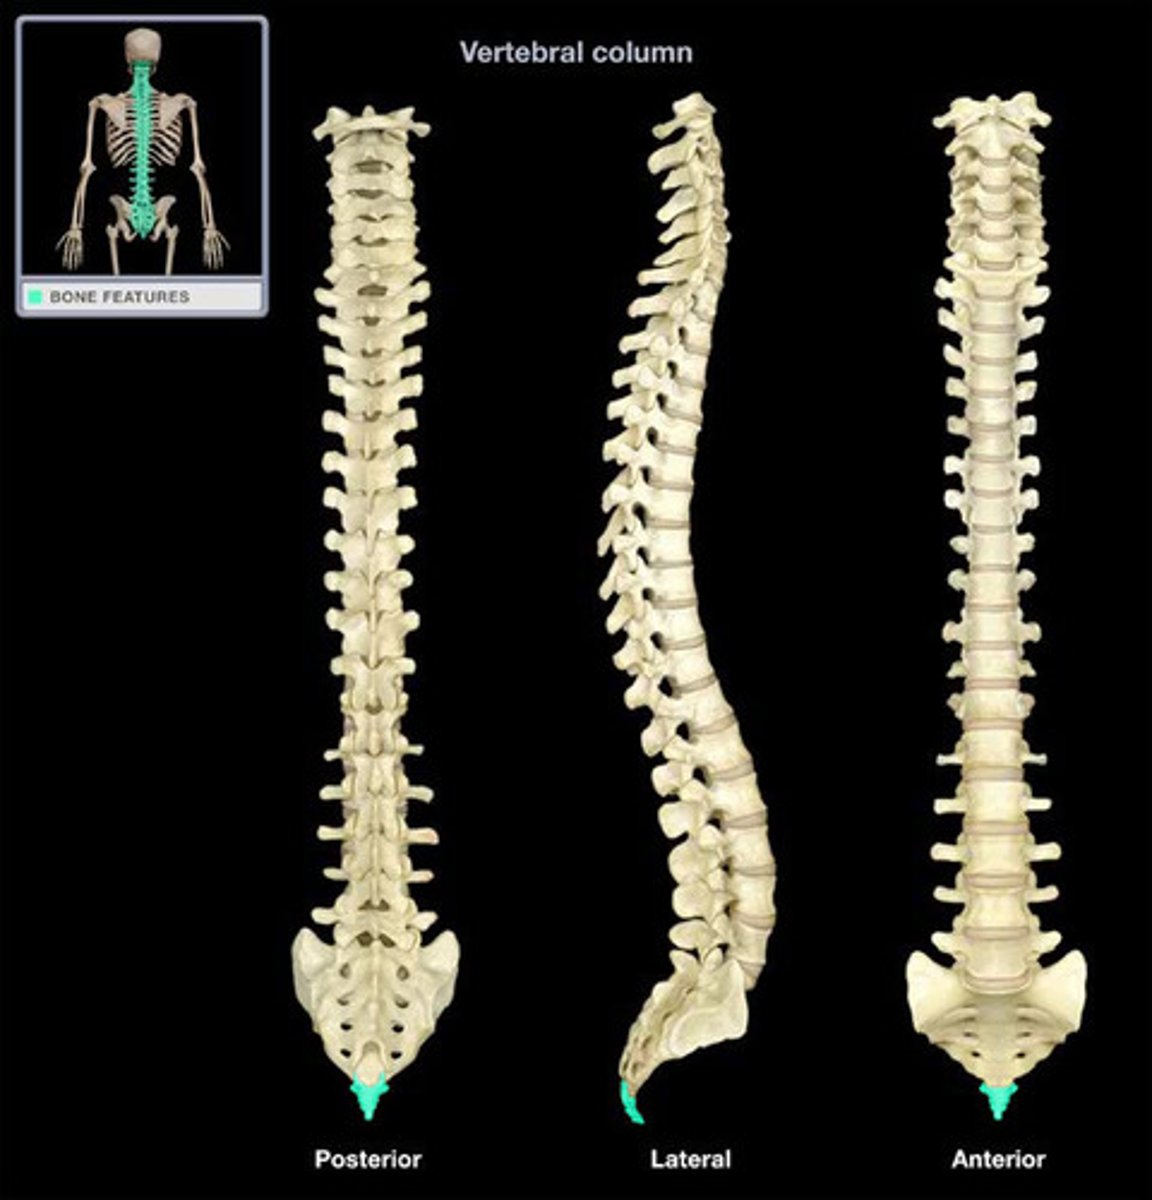

Spine (C/T/L), Sacrum & Coccyx

What are the sections of the vertebral column?

cervical, thoracic, lumbar, sacrum, coccyx